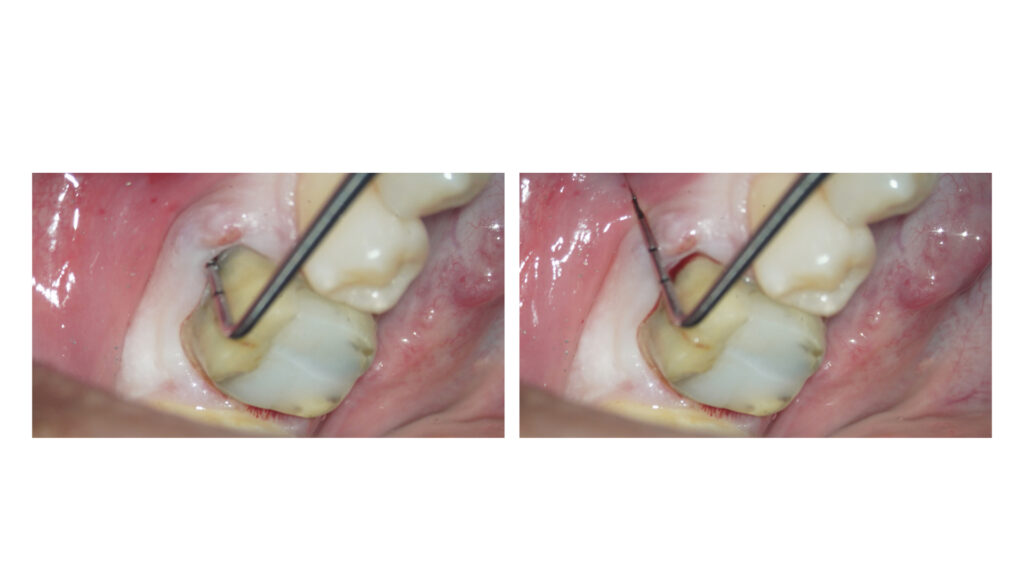

左下奥歯に違和感を訴えて来院されました。

銀歯の周囲に腫れを認めます。

歯周ポケットは深く歯根破折のため抜歯判定となりました。

メンブレン設置に向けてエンベロープ形成を事前に行なっています。